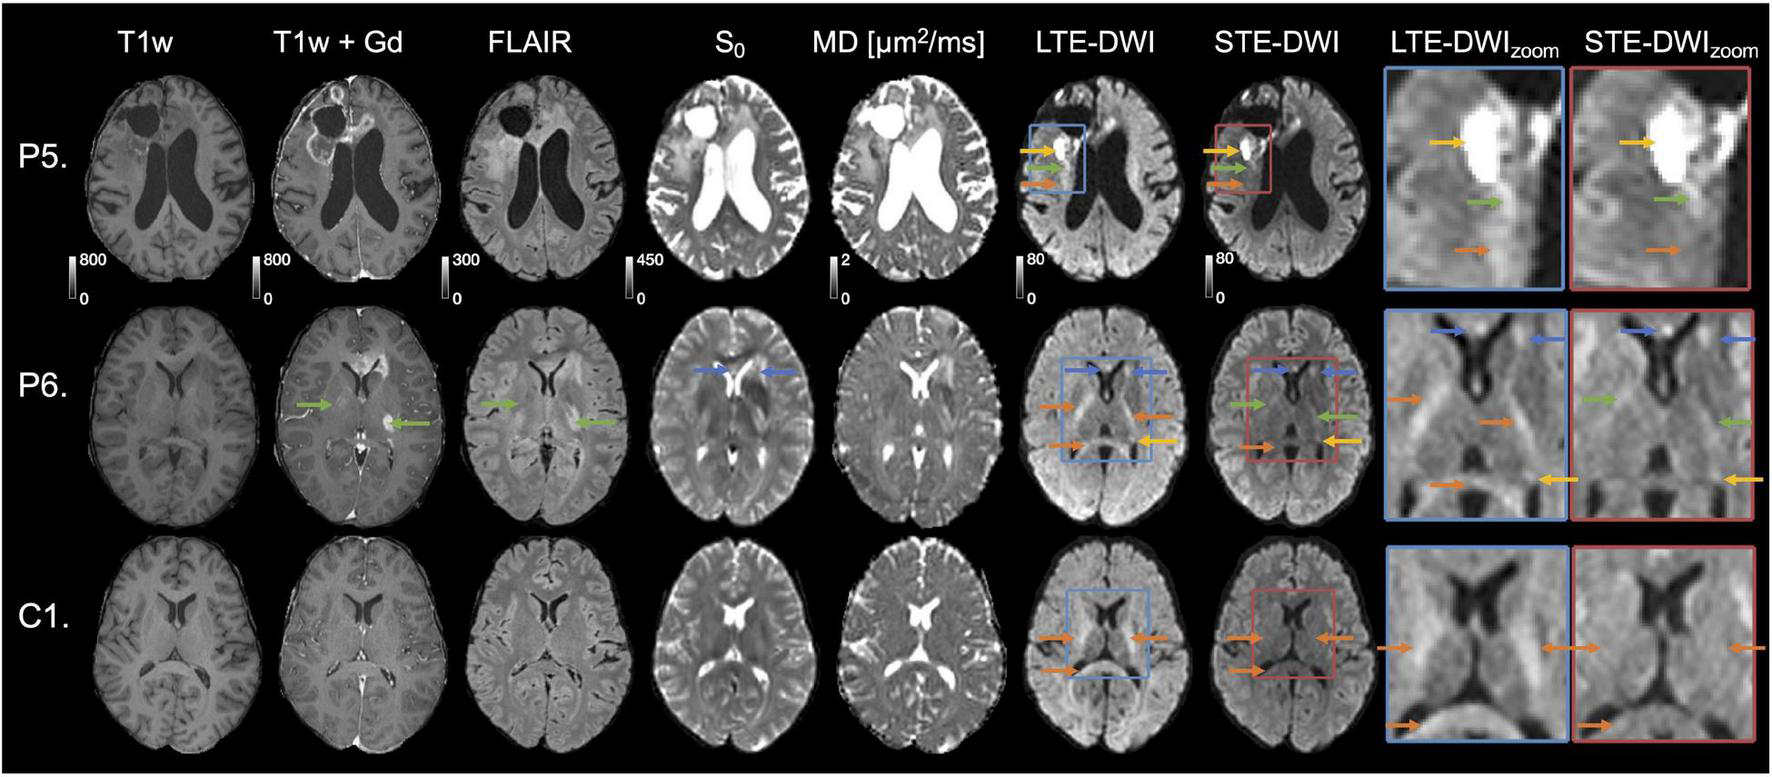

Interpretation challenges: Examples where inclusion of STE-DWI could improve diagnostic confidence. The top row (patient P5) shows images obtained after initiation of therapy (Optune) from a 62-year-old male diagnosed with glioblastoma grade IV (wild-type IDH, non-methylated MGMT). The tumor-related hyperintensity (yellow arrows) is with LTE-DWI surrounded by what appears to be hyperintense white matter (orange arrow). However, only parts of what may be interpreted as hyperintense white matter on LTE-DWI is attenuated with STE-DWI (orange arrow). The part closer to the main lesion remains hyperintensed with STE-DWI (green arrow), which suggests that it is a tumor-related hyperintensity. The middle row (P6) shows images obtained to confirm tumor progression in a 31-year-old male diagnosed with glioblastoma grade IV (mutated IDH). Several LTE-DWI and STE-DWI hyperintensities can be observed, however, STE-DWI suppresses those related to white matter (orange arrows) and, thereby amplifies the contrast of those that are not white-matter related. Out of these, two may be due to T2 shine-through effect (blue arrows). Some of the STE-DWI hyperintensities were “hidden” with LTE-DWI under the white matter-related hyperintensities (green arrows). The STE-DWI suggests that they may be tumor-related hyperintensities coming from tumor cells spreading along the white matter tracts. Note that these tracts are surrounded by Gd-enhancements and T2 FLAIR hyperintensity (green arrows). The bottom row shows images obtained in a subject (C1) without relevant MRI abnormalities in the region evaluated to illustrate that—unlike in the previous case—all white-matter-related hyperintensities seen with LTE-DWI disappear with STE-DWI (orange arrows).

Figure 5 illustrates two cases (P5 and P6), where STE-DWI provides a complementary contrast to LTE-DWI, as well as a patient without relevant MRI abnormalities (C1) as a reference. In the top row (P5), STE-DWI and LTE-DWI reveal different regions as hyperintense. One region is strongly hyperintensed in both LTE-DWI and STE-DWI (yellow arrow), while another region is weakly hyperintensed in LTE-DWI, but isointense in STE-DWI (orange arrow). A third region is weakly hyperintensed on both LTE- and STE-DWI (green arrows). This third region might be regarded as white-matter-related when viewing LTE-DWI only. However, the bright appearance of STE-DWI suggests that it is tumor-related. In the second patient (P6), LTE-DWI and STE-DWI show multiple regions as hyperintense, where some, but not all, may be considered as malignant tissue. Two regions are strongly hyperintensed on both LTE-DWI and STE-DWI (blue and yellow arrows). Three regions are hyperintensed on LTE-DWI but not on STE-DWI, as it suppresses white matter-related hyperintensities (orange arrows). Importantly, STE-DWI shows two hyperintensities (green arrows) that were not visible on LTE-DWI. This suggests that STE-DWI, unlike LTE-DWI, may visualize lesions that would otherwise be hidden in white matter. These two hyperintensities are also indicated in the T1w+Gd (gadolinium) and T2 FLAIR images (green arrows). The gadolinium enhancements also point to a malignant process and further support this interpretation. For comparison, the third row shows a slice from a patient without relevant MRI abnormalities (C1) in the same location, as that in the second patient. Again, we see white matter-related hyperintensities (orange arrows) in LTE-DWI that disappear and become isointense with the surrounding tissue in STE-DWI.